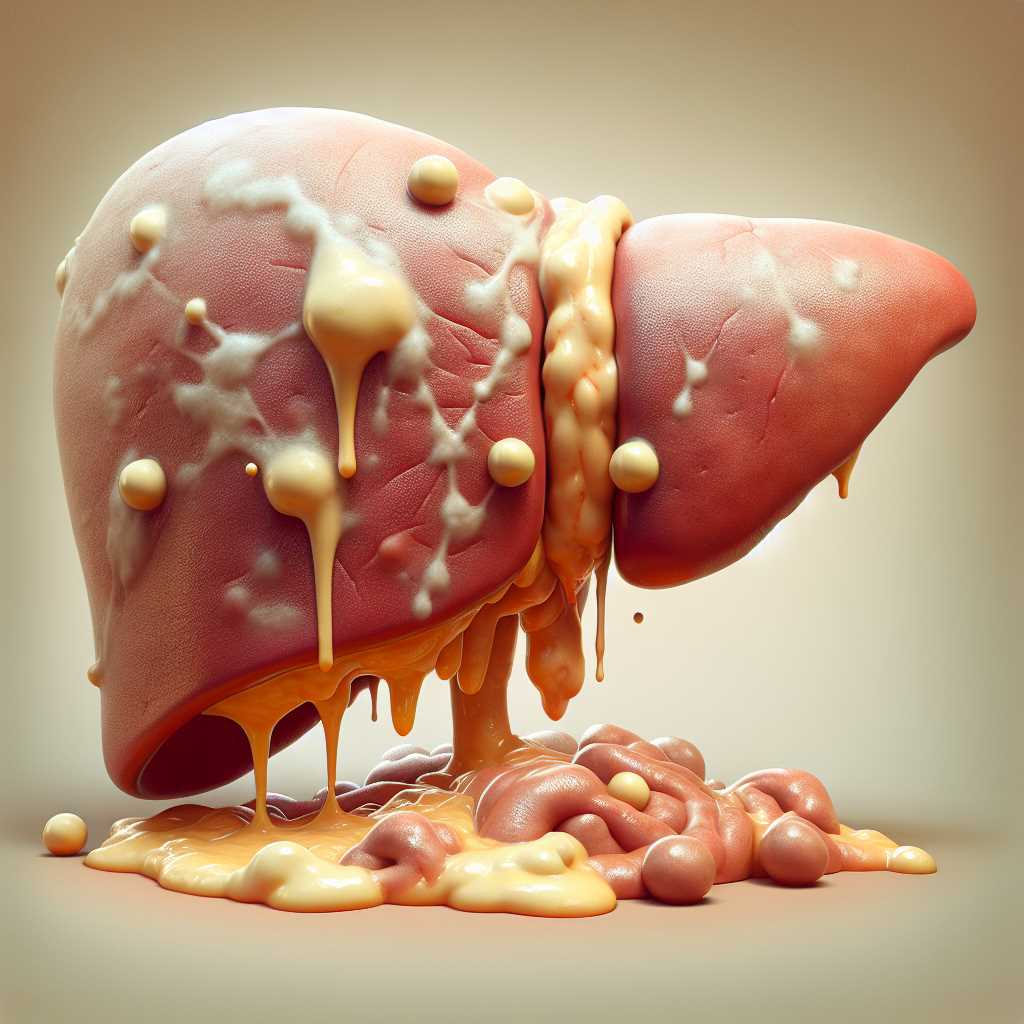

En Perú, alrededor del 30% de la población padece hígado graso, una enfermedad silenciosa que puede tardar más de 20 años en mostrar síntomas, pero que es la principal causa de cirrosis hepática en el país. El hígado cumple funciones vitales como filtrar toxinas, procesar nutrientes y almacenar energía.

Cuando acumula demasiada grasa, se deteriora su funcionamiento, lo que puede derivar en enfermedades graves como cirrosis o incluso cáncer de hígado. Una alternativa natural que puede ayudar a cuidar este órgano es el toronjil (Melissa officinalis), una planta conocida por sus propiedades digestivas, antiinflamatorias y protectoras del hígado.

Contiene antioxidantes y compuestos como el ácido rosmarínico, que favorecen la depuración hepática, reducen la inflamación y previenen el daño celular, ayudando así a tratar el hígado graso y prevenir su avance hacia cirrosis.

El toronjil también mejora la función enzimática del hígado y ayuda a metabolizar mejor las grasas, además de proteger contra el estrés oxidativo.